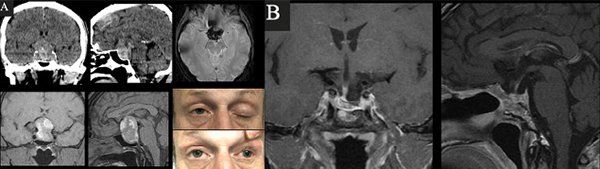

Caso 1. A. Preoperatorio. Varón de 63 años, hipertenso y antiagregado con AAS que consultó por cefalea, náuseas, vómitos y síncope. Al examen físico presentaba disminución de la AV en ojo izquierdo + ptosis palpebral y midriasis izquierdas. En la TC y RM de cerebro e hipófisis se evidenciaba una lesión selar con componente hemorrágico y edema de la vía óptica. El CVC evidenciaba hemianopsia temporal izquierda y cuadrantopsia superior derecha. B. Postoperatorio. RM que demuestra resección completa y CVC normal.

Caso 2. A. Preoperatorio. Varón de 54 años que consultó por cefalea, náuseas y vómitos. Al examen físico presentaba disminución de la AV y III par completo izquierdo +. En la TC y RM de cerebro e hipófisis se evidenciaba una lesión selar-supraselar voluminosa con contenido hemático. B. Postoperatorio. RM que demuestra resección completa de la lesión.

Caso 3. A. Preoperatorio. Paciente de 31 años, anticoagulado por TEP derivado de otro hospital por disminución aguda de la visión. La RM de hipófisis evidenciaba una lesión selar-supraselar voluminosa con un gran contenido hemorrágico. El CVC objetivaba amaurosis derecha y hemianopsia izquierda. B. Postoperatorio. RM que demuestra resección completa de la lesión y CVC con mejoría parcial.